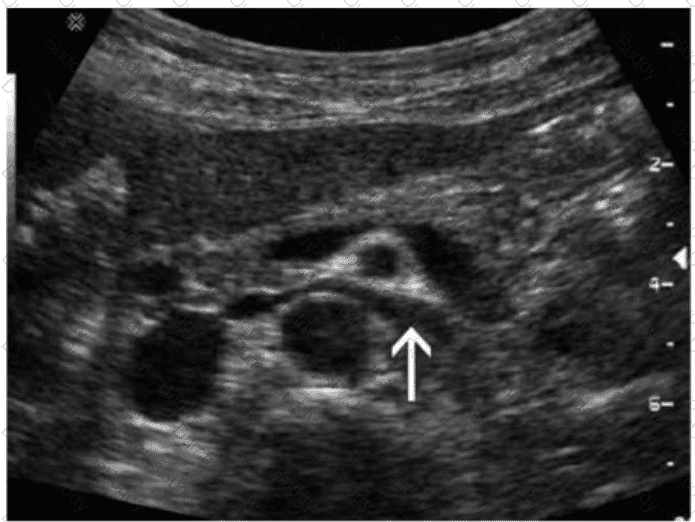

Which congenital disorder is most consistent with the finding identified by the arrow on this image?